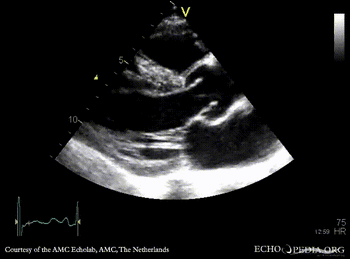

M-Mode through aortic valve PLAX: Color Doppler signal shows severe aortic regurgitation